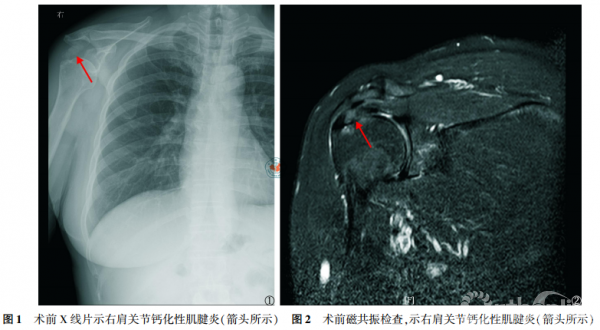

患者入院后减少患侧肩关节活动,予口服非甾体类消炎药(non-steroidal anti-inflammatory drugs,NSAIDs)药物西乐葆200 mg,一日两次,并予局部冰敷,收集术前美国加州大学肩关节评分(University of Californiaat Los Angeles,UCLA评分),完善相关检查,如肩关节X线检查(图1),肩关节磁共振检查(图2)和手术准备。

典型病例 女性患者,49岁,因“右肩关节疼痛、活动受限5d”入院,查体见右肩关节局部压痛,以冈上肌处明显,右肩关节主动活动范围受限,被动活动范围基本正常,Neer撞击征(+),术前X线片示右肩峰下一巨大密度增高团块(图1),磁共振示右冈上肌腱内一信号增高团块(图2),诊断考虑“右肩关节钙化性肌腱炎”,行“右肩关节关节镜探查清理+冈上肌腱钙化灶清理+肩袖修补术”,术中清理右肩冈上肌腱内牙膏样的乳白色稠状物,即钙质沉积(图3),见肌腱裂口超过肩袖厚度的1/2,予2枚铆钉修补肩袖,术后复查右肩关节X片(图4)。术后患者疼痛程度明显减轻,随访9个月,UCLA评分由术前的11畅5分提高至33畅5分,且无出现术后并发症。